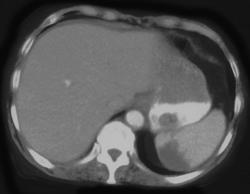

Splenic Vein Occlusion With Collaterals